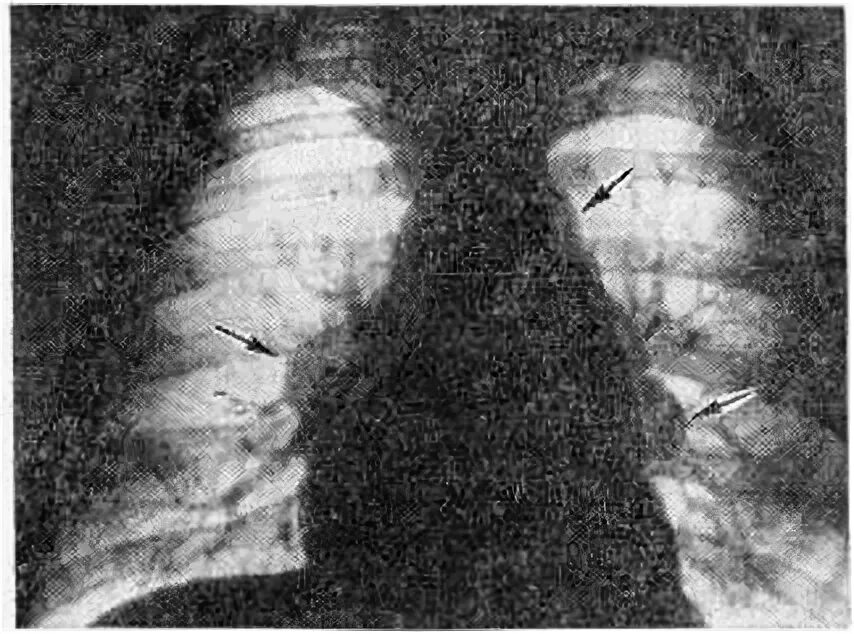

Что такое лимфаденопатия легких и как лечить